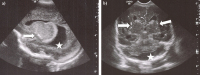

Schwere kongenitale Zytomegalieinfektion durch frühe Virusreaktivierung in der Schwangerschaft